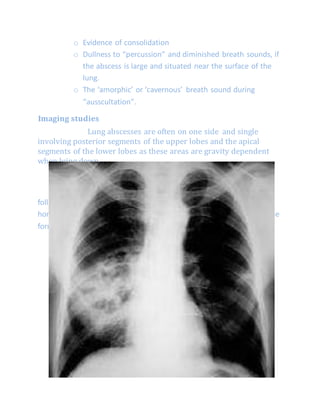

Imaging studies

Lung abscesses are often on one side and single

involving posterior segments of the upper lobes and the apical

segments of the lower lobes as these areas are gravity dependent

when lying down.